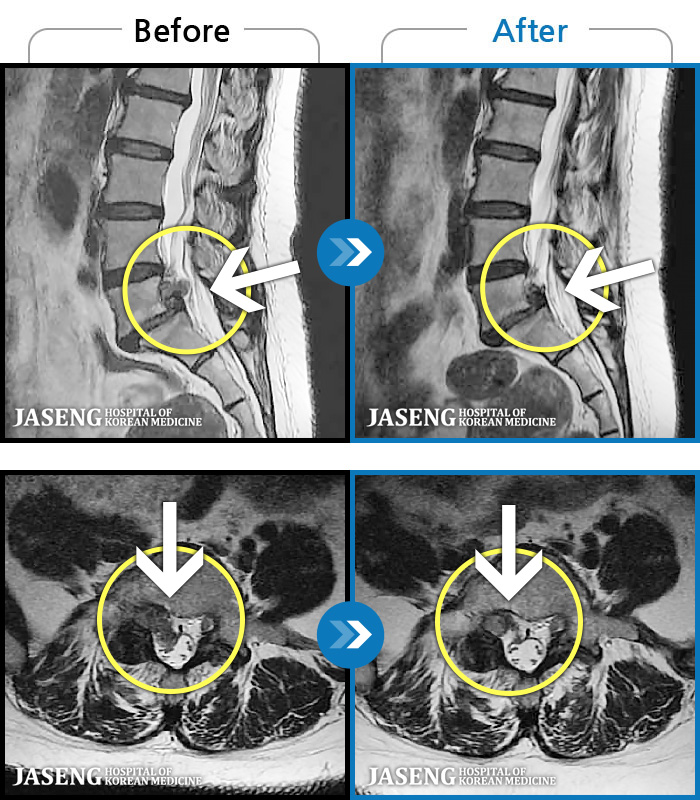

123 MRI ũ ʸ Ȯϼ.

[뱸] 19.11.28~25.05.06